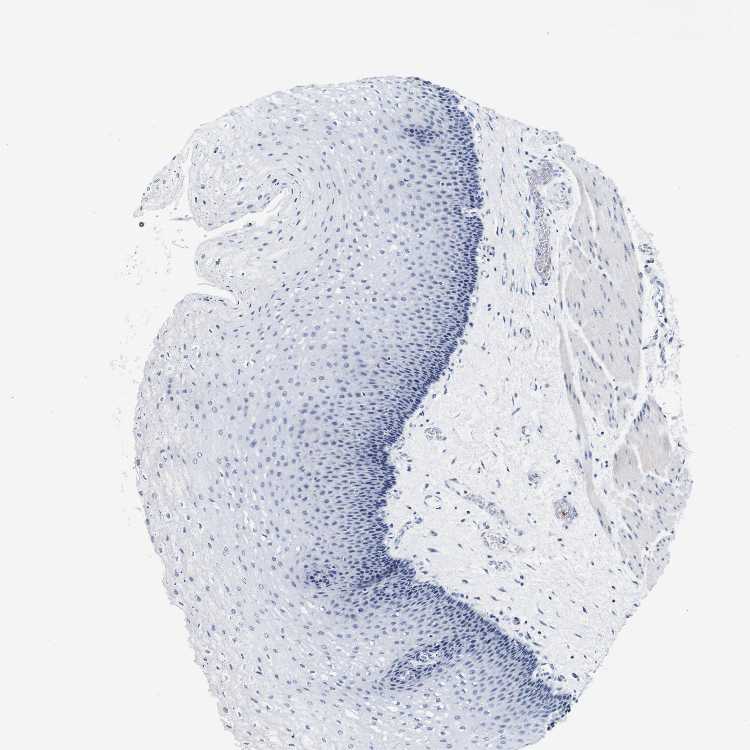

ESOPHAGUS - Antibody stainingi

Antibody staining in the annotated cell types in the current human tissue is reported as not detected, low, medium, or high, based on conventional immunohistochemistry profiling in selected tissues. This score is based on the combination of the staining intensity and fraction of stained cells.

Each image is clickable and will lead to virtual microscopy that enables deeper exploration of all samples and also displays staining intensity scores, fraction scores and subcellular localization as well as patient and tissue information for each sample.

Antibody HPA013316Antibody CAB002496

Squamous epithelial cells Not detectedNot detected